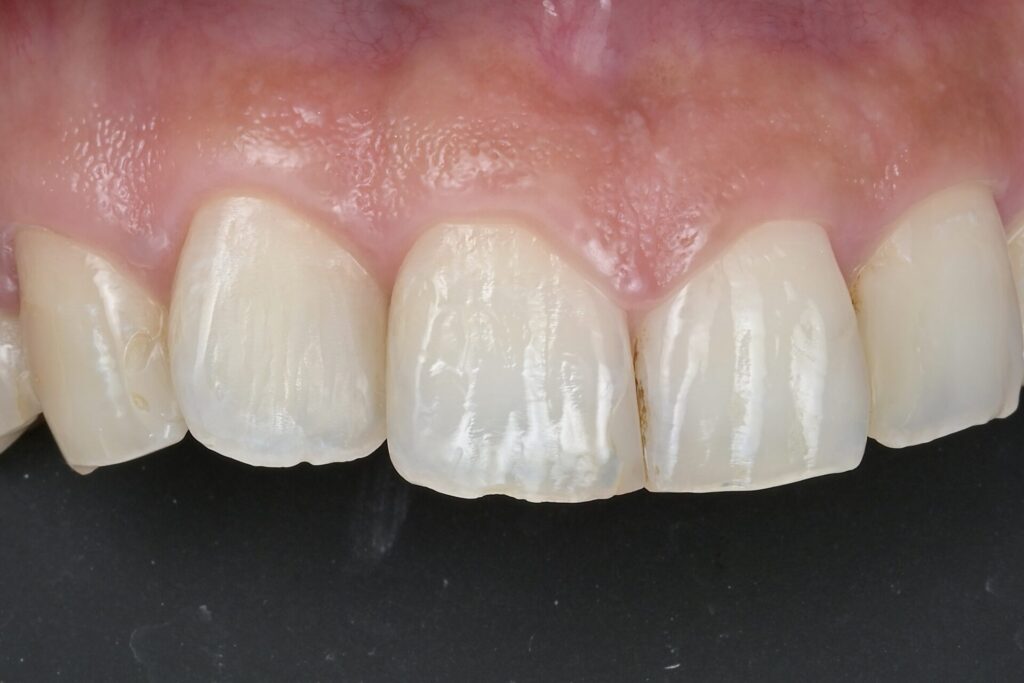

神経を取りたくない・MTAセメント・歯髄保存療法虫歯の治療・ダイレクトボンディング

30代 虫歯治療 VPT(歯髄温存療法)ダイレクトボンディング #66

02虫歯治療(ダイレクトボンディング)

ダイレクトボンディングは、歯の欠損や小さな虫歯を即座に修復する方法です。歯と同色の材料を直接歯に盛り付け、自然な見た目と機能を取り戻します。